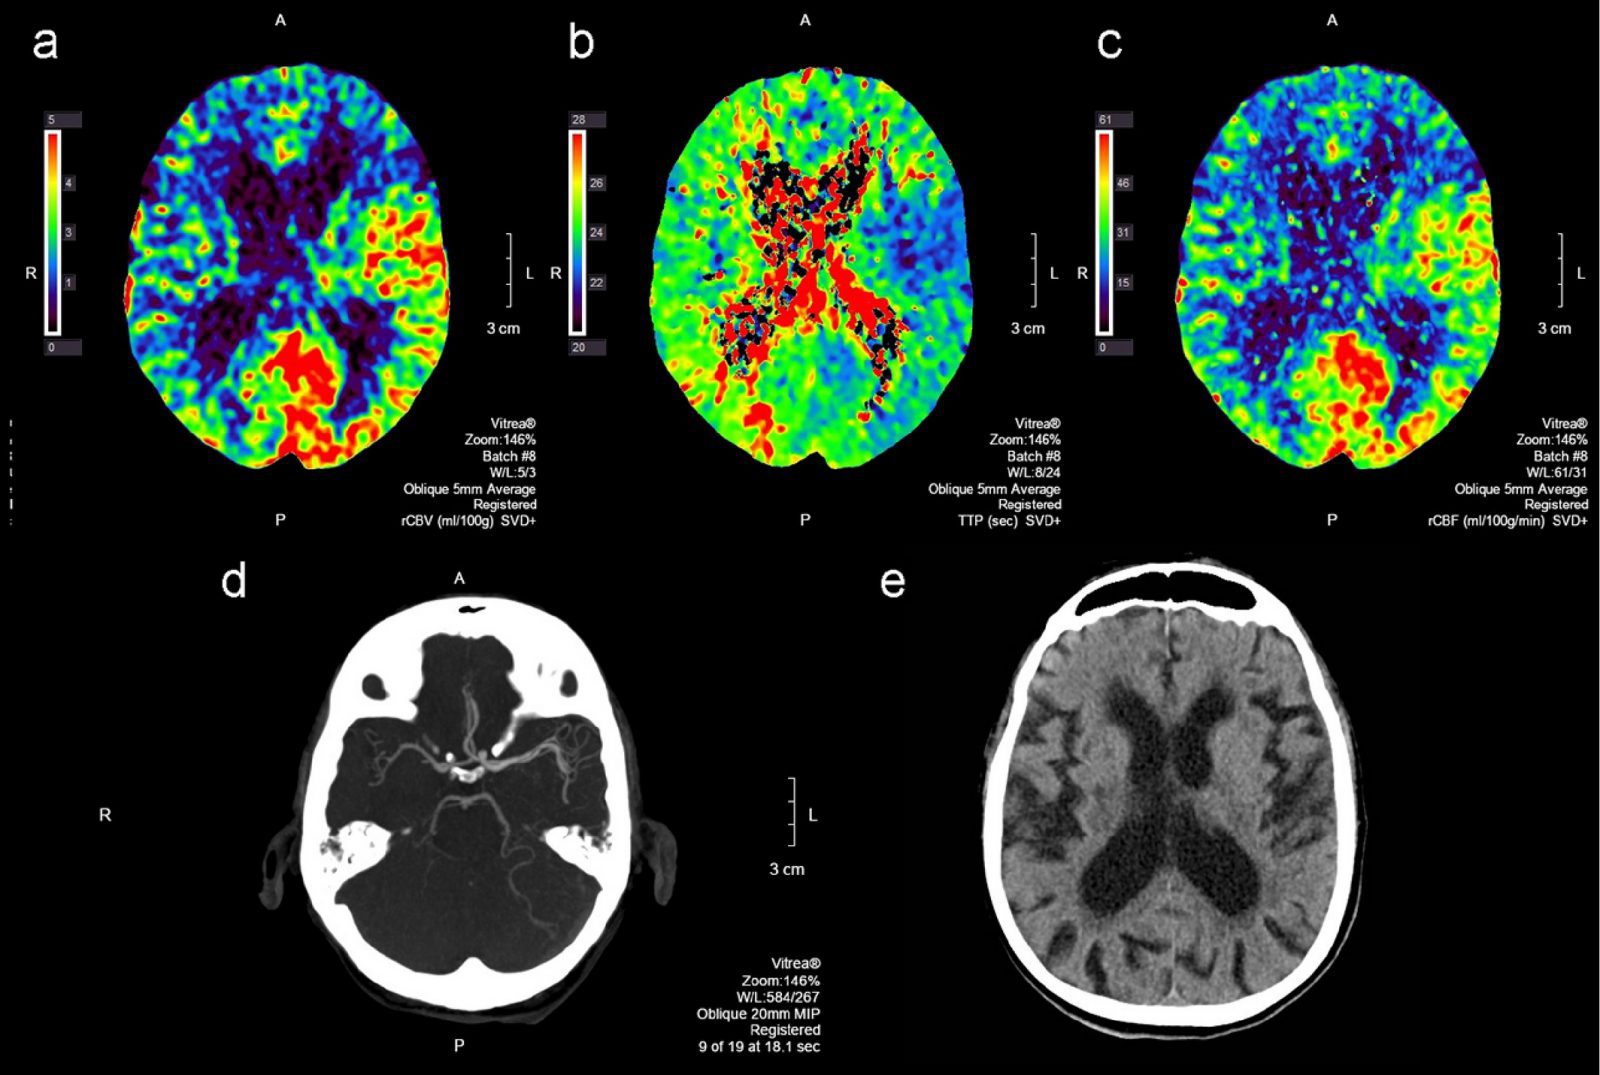

Perfusion Imaging Perfusion is a fundamental biological function that refers to the delivery of oxygen and nutrients to tissue by means of blood flow. Perfusion MRI is sensitive to microvasculature and has been applied in a wide variety of clinical applications, including the classification of tumors, identification of stroke regions, and characterization of other diseases. Perfusion MRI techniques are classified with or without using an exogenous contrast agent. Bolus methods, with injections of a contrast agent, provide better sensitivity with

The calculation of perfusion analysis is based on measurements taken while the bolus travels through the blood system. The starting point is the arterial input function (AIF), measured at the artery before the contrast agent bolus travels through the region of interest (ROI). Perfusion analysis from first-pass contrast enhancement kinetics requires modeling tissue contrast exchange. To streamline the integrated analysis of perfusion parameters, there is a present a visual analysis approach incorporating pre-processing and statistical methods. Motion correction and noise